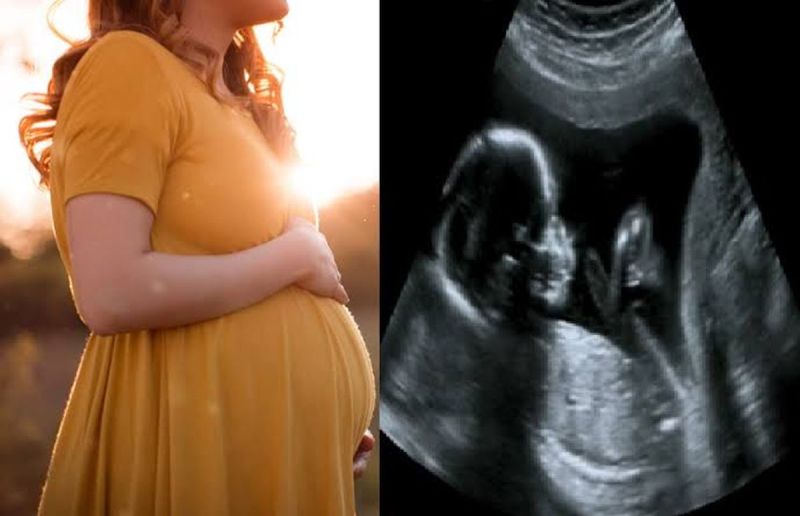

Karnataka में अवैध गर्भपात पर कड़ी कार्रवाई के बावजूद, कन्या feticide बेरोकटोक जारी है। अवैध लिंग परीक्षण पर शिकंजा कसते हुए स्वास्थ्य विभाग ने अब ultrasonography room के अंदर गर्भवती महिला के साथ किसी भी अटेंडेंट के प्रवेश पर रोक लगा दी है। इसके अलावा, अल्ट्रासाउंड कक्ष में अतिरिक्त मॉनिटर के प्रदर्शन पर भी प्रतिबंध लगाया गया है।

इस संबंध में जारी परिपत्र में स्वास्थ्य विभाग ने सभी ultrasound scanning centers और अस्पतालों को स्कैनिंग कक्ष के बाहर किसी भी अटेंडेंट को अंदर आने की अनुमति नहीं है संदेश वाले बोर्ड लगाने के निर्देश दिए हैं। सभी स्कैनिंग केंद्रों को नए निर्देशों का सख्ती से पालन करने के निर्देश दिए गए हैं। उल्लंघन के मामलों में सख्त कार्रवाई होगी।

PCPNDT Task Force के प्रमुख और स्वास्थ्य आयुक्त रणदीप डी. ने बताया कि निरीक्षण के दौरान स्कैनिंग केंद्रों पर कई उल्लंघन देखे गए हैं। परिपत्र का उद्देश्य गर्भधारण पूर्व और प्रसव पूर्व निदान तकनीक (पीसीपीएनडीटी) अधिनियम, 1994 को प्रभावी ढंग से लागू करना है। हाल ही में पीसीपीएनडीटी कार्यशाला में कई radiologist और स्त्री रोग विशेषज्ञों ने चिंता जताई कि थी कि गर्भवती महिला के साथ परिजन अल्ट्रासोनोग्राफी कक्ष में जाते हैं और अल्ट्रासाउंड प्रक्रिया का वीडियो बनाते हैं या तस्वीरें लेते हैं। उन्होंने यह भी चिंता व्यक्त की थी कि रिकॉर्ड किए गए video का उपयोग भ्रूण के लिंग की पहचान करने के लिए किया जाता है। यह धारा 5, उपधारा (2) के तहत पीसीपीएनडीटी अधिनियम का उल्लंघन है।

राज्य पीसीपीएनडीटी के नोडल अधिकारी विवेक दोराई ने कहा कि राज्य में एक नया चलन उभर रहा है, जिसमें भ्रूण का लिंग निर्धारित करने के उद्देश्य से अल्ट्रासाउंड प्रक्रिया के वीडियो बनाए जाते हैं। विदेश में रहने वाले अपने दोस्तों या रिश्तेदारों के साथ साझा कर लिंग निर्धारित करते हैं। उन्होंने कहा कि अल्ट्रासाउंड कक्ष में एक अतिरिक्त मॉनिटर होता है, जो गर्भवती महिलाओं को अल्ट्रासाउंड प्रक्रिया देखने में सक्षम बनाता है। कभी-कभी, रेडियोलॉजिस्ट, बिना कुछ कहे या कोई इशारा किए, लिंग का संकेत देने के लिए भ्रूण के निजी अंगों पर इशारा कर सकते हैं। इसलिए पीसीपीएनडीटी अधिनियम के प्रभावी क्रियान्वयन के लिए अल्ट्रासाउंड कक्ष में अतिरिक्त मॉनिटर का प्रदर्शन वर्जित है।